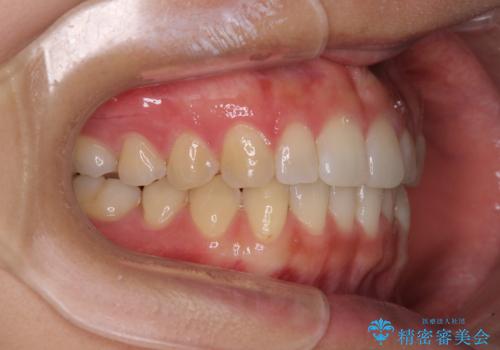

インプラントによる補綴治療とインビザライン矯正

- 抜歯が必要と診断された奥歯を気にして来院された患者様です。

抜歯の上インプラントによる補綴治療を行うこととなりましたが、前歯の叢生も気になるとのことで並行して矯正治療を行うこととしました。

歯列不正は軽微であったので、インビザラインによる矯正治療とし、矯正治療中にインプラント埋入を行う予定としました。

痛みがないので、ボロボロのまま放置していましたが、抜歯後は汚れが溜まりにくくなりスッキリとしたようです。

前歯のデコボコも解消され、ブラッシングが楽になりました。